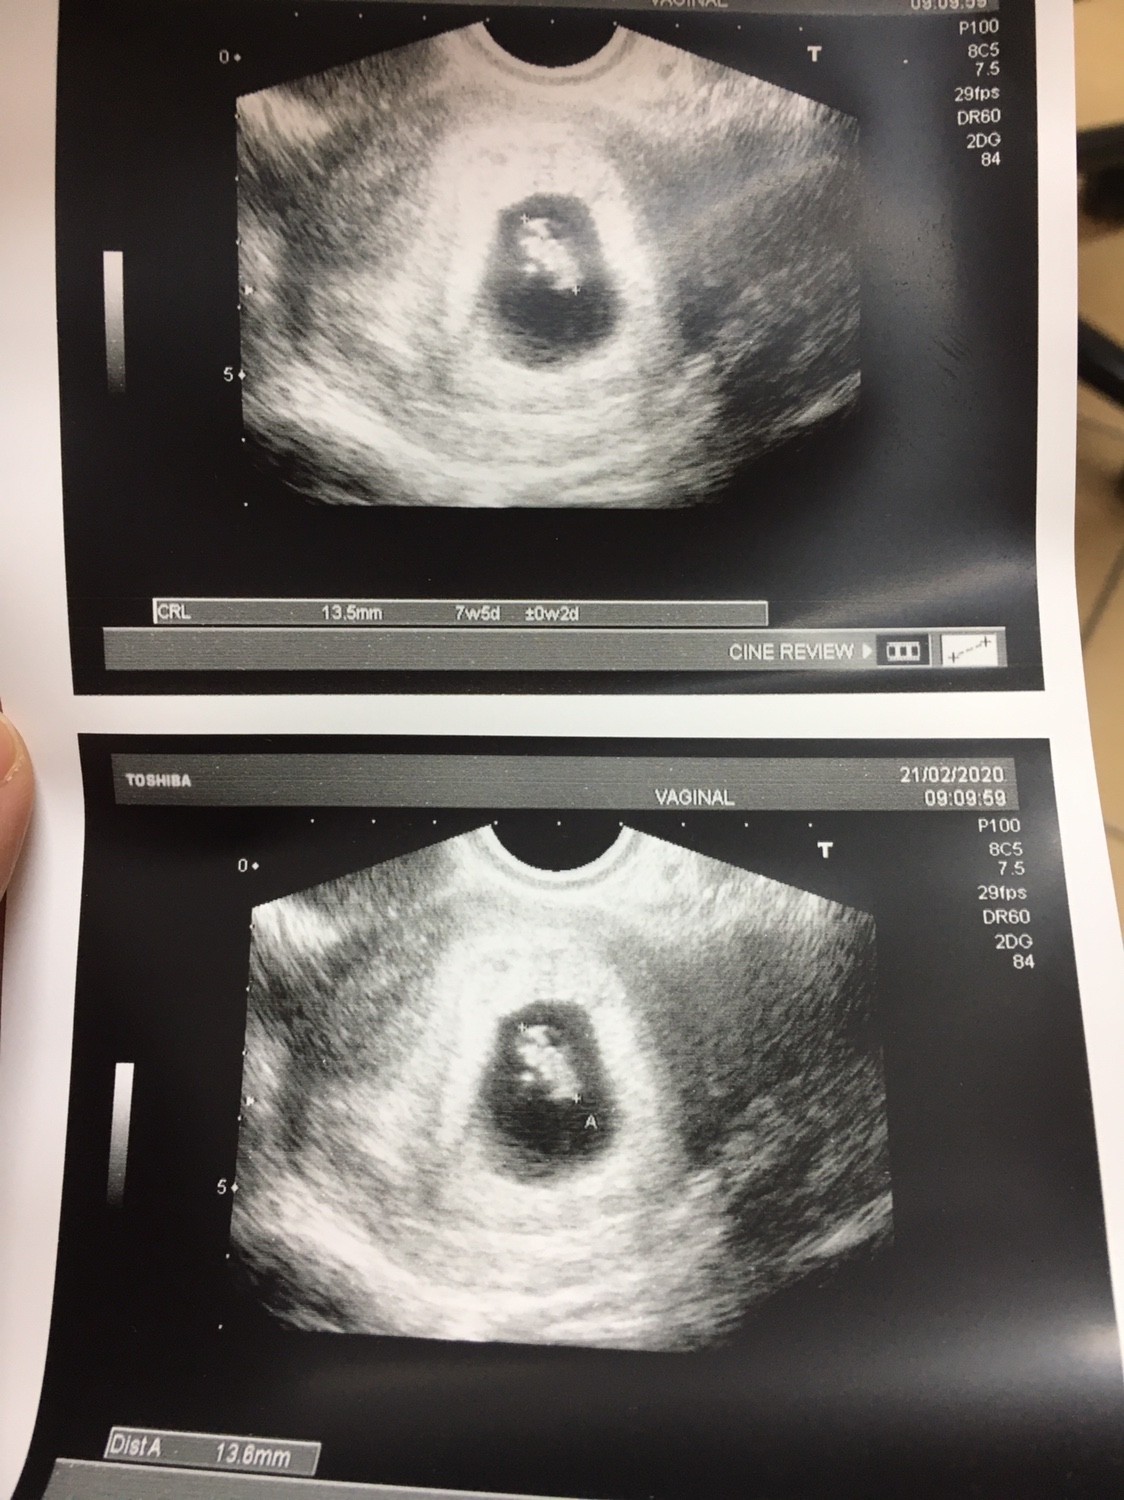

Zobacz załącznik 1083500

Hej dziewczyny ja już po wizycie serduszko dalej stuka. Trochę jaszczurka mi nadrobiła z tygodniami z om 7t3d a usg 7t5d wiec nawet się zagalopowała [emoji23]wszystko jest ok dostałam badania na krew.

Następna wizyta 20.03